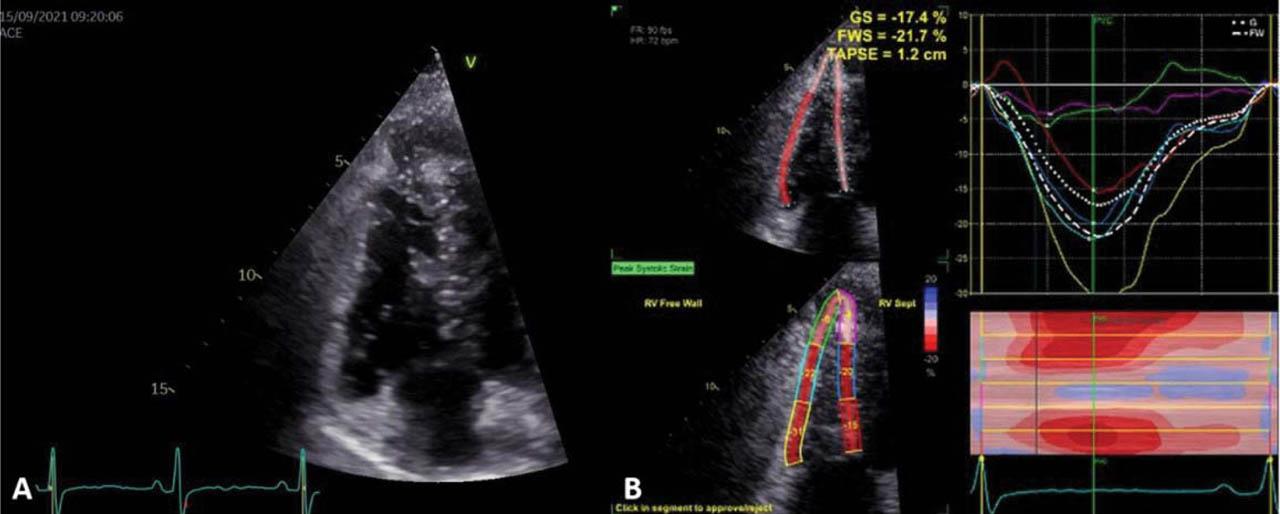

Figure 3

(A) Transthoracic echocardiography, apical RV-focused: normal size RV (B) Transthoracic 2D speckle-tracking echocardiography: slightly reduced RV longitudinal strain.